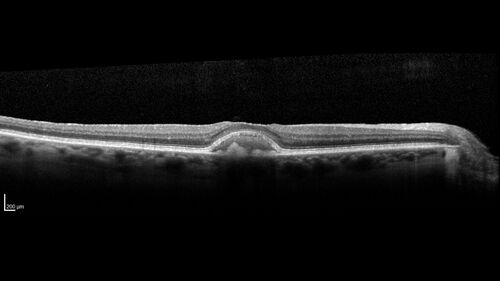

Pattern Dystrophy with Collapsed Vitelliform

74 year old female with vision loss in eye with collapsed vitelliform lesion.

Collapsed Vitelliform Pattern Dystrophy